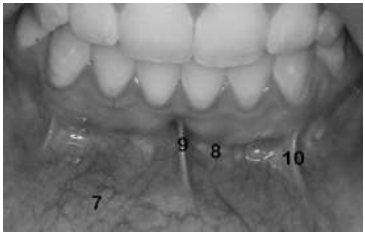

INSTRUÇÃO: Considere a imagem a seguir para responder a questão:

INSTRUÇÃO: Considere a imagem a seguir para responder a questão: